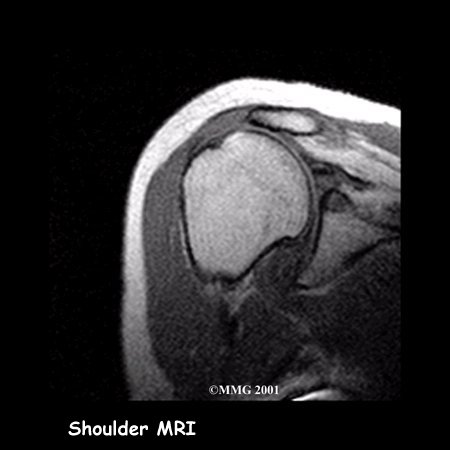

Your doctor may ask you to have a magnetic resonance imaging (MRI) scan.

An MRI scan is a special imaging test that uses magnetic waves to create pictures of the shoulder in slices. The MRI scan shows tendons as well as bones. This test is painless and requires no needles or injections.

Today, the MRI scan is the most common test used to evaluate the shoulder and determine whether surgery is necessary. Your surgeon will be looking for details of your rotator cuff tear and checking for other problems. As mentioned earlier, a tear usually doesn't occur unless the rotator cuff is already weakened by some other problem. Other potential problems include: